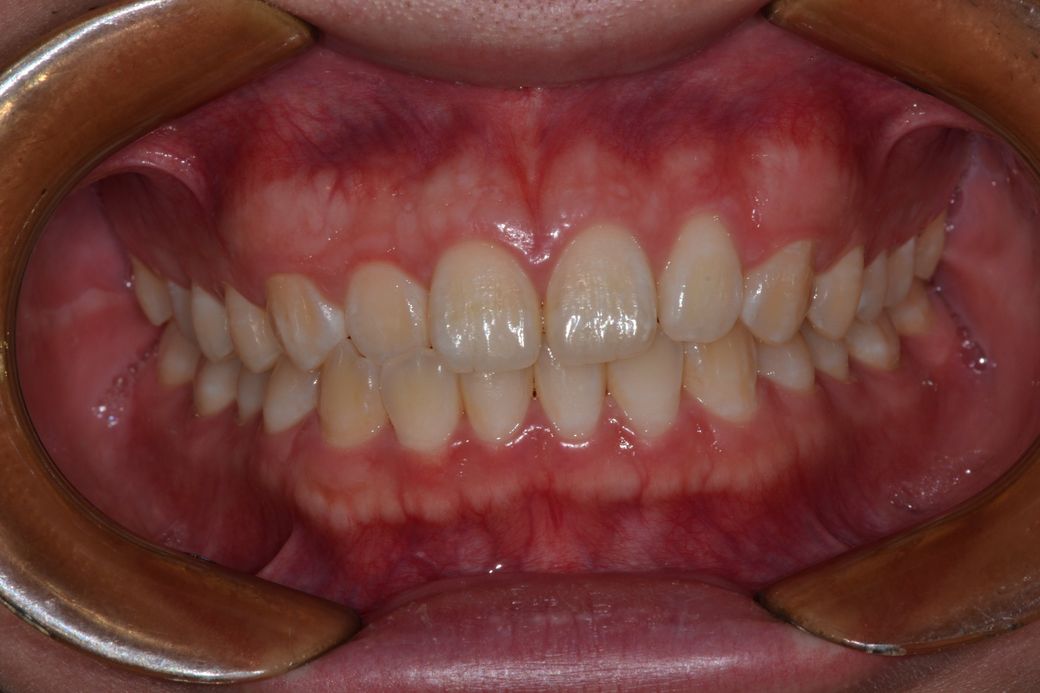

• 1번 째 사진

세가지 치과 모두 맞는 말입니다. 지금 보여주신 자료를 종합해보면 경미한 3급 부정교합입니다.

이 상태에서 교정도 가능하고 양악도 가능하지만 치료 이후 변화되는 모습에는 한계가 있습니다. 또한 부정교합 및 골격부조화가 심하지 않으므로 심미적으로 불편감이 없다면 3번 치과처럼 치료하지 않아도 됩니다. 물론 심미적으로 문제가 된다고 생각한다면 이때는 두가지 방법 모두 가능합니다.

하지만 개인적으로는 3번째 치과의 견해처럼, 교정이 필요해보이진 않습니다. 우측 측절치가 반대교합이긴 하지만, 교정여부는 본인의 심미적인 개선의 의지에 따라서 달라질 것 같습니다.